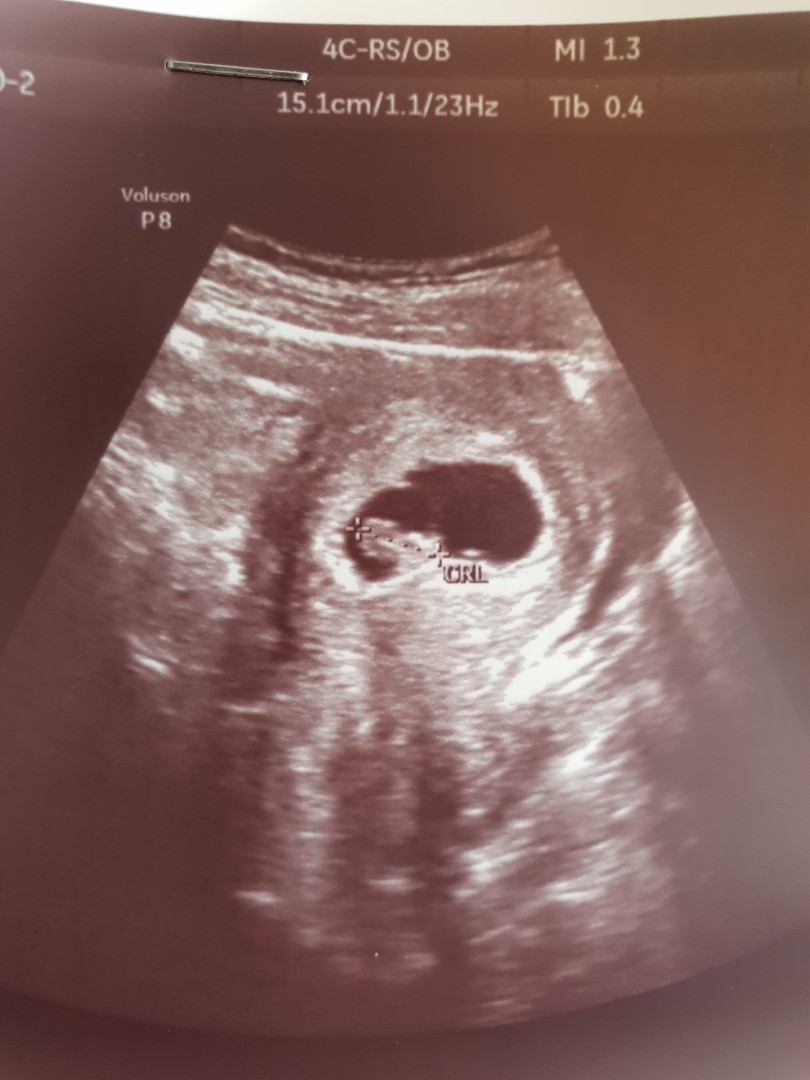

อัลตร้าซาวด์

ขอดูใบอัลตร้าซาวด์ของแม่ๆตัวเล็กอายุครรภ์ประมาณ7วีคหน่อยค่ะ

7วีคค่ะ

7วีคค่ะคุณหมอซาวด์ผ่านช่องคลอด น้องยังเล็กเท่าเม็ดถั่วอยู่เลยค่ะ😊